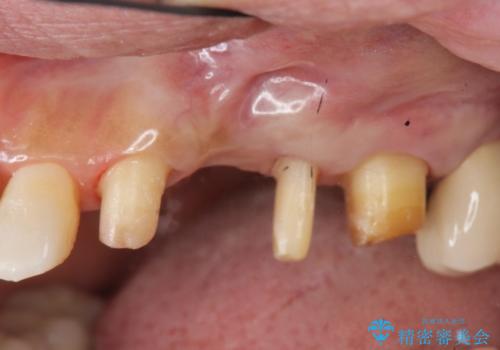

- 全体的に歯が揺れ、このままでは全て歯を失うのではないかと怖くなり歯周病治療を希望され来院されました。

歯列不正による第一小臼歯の骨吸収が認められ、機能咬合力の回復、大きな側方力に連結することで抵抗することのできるブリッジ補綴を選択しました。

歯周病による深いポケット・大きな側方力・短い臨床歯根・欠損の補綴、これらの問題を解決するために歯周補綴を兼ねたブリッジを選択しました。